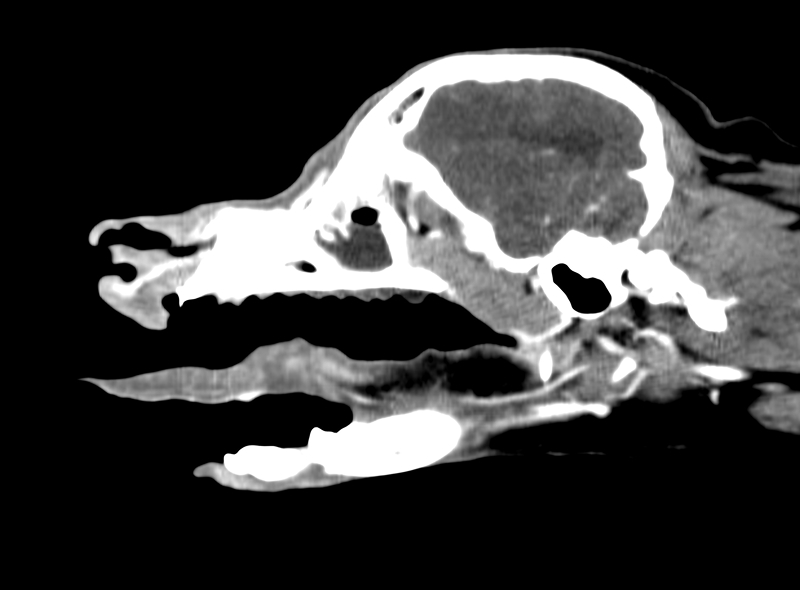

舌に発生した癌の浸潤を判定するために実施したCT検査画像

腫瘍の確定診断がついた場合、次にその腫瘍のステージ判定が必要となります。

ステージ判定とは、腫瘍の広がりを把握することを指します。腫瘍の広がりには2種類あります。

まず1つ目として、良性の病変とがんを比較した時に、患部でどの程度広がっているかで違いがあります。良性の病変では発生した場所で、見た目以上には広がっていないことが殆どですが、がんでは見た目以上に腫瘍の周りに広がっている場合があります。これを浸潤と言います。

2つ目は、他の臓器に広がっていないかどうかです。良性の病変では他の臓器に病変を作ることはあまりありませんが、がんでは、がん細胞が周囲の血管やリンパ管に入りこみ、他の臓器に広がることがあります。これを転移と言います。